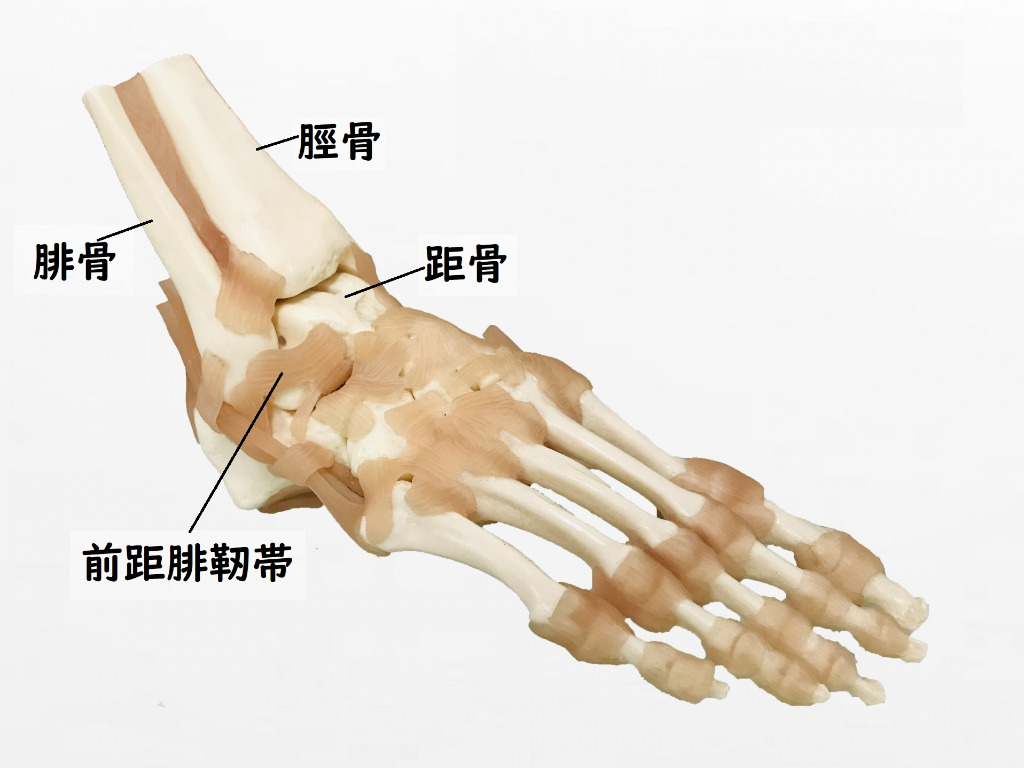

足関節捻挫について

足関節の捻挫は最も発生頻度の高い外傷で、程度の差はあれどほとんどの方が経験があるのではないかと思います。

足関節の捻挫には足部を内側に捻る内反捻挫と外側に捻る外反捻挫があり、当然それぞれで損傷する靭帯も異なりますが足関節の構造上内反捻挫が圧倒的に多いと言われています。

足関節の内反捻挫は足関節を正常な可動範囲を超えて内側に捻ることによって前距腓靭帯という腓骨と距骨を結ぶ靭帯が最も高頻度で損傷します。

前距腓靭帯が損傷すると足関節を動かす時に距骨を正常な位置に留める力に障害が起きてしまうため足関節の安定性に大きな影響を及ぼします。

関節が動く際には当然関節を構成する骨の動きが伴いますので、足関節を内反する際にも当然足関節を構成する脛骨、腓骨、距骨にも動きが生じます。

足関節の内反は底屈(つま先を床に向けて下げる動き)、外旋(回外)、内転の複合運動となっていて、内反の際には脛骨、腓骨には軽度の内旋、腓骨には内旋に加えて下方に下がり、距骨には前方と内方へと滑る動きが起こります。

この内反によって起こる骨の移動によって、足関節は安定性が低い状態になります。

正常であれば内反をやめるとそれぞれの骨は正常な位置に戻り、外反の際には反対の動きをするのでそれらの動きがちゃんと出来ていれば足関節は正常な状態と言えます。

しかし、足関節の内反捻挫になると捻挫した時に加わった力によって内反の形で固められてしまい、足関節が不安定な構造で固められてしまうことになりますので、安定する通常の状態に戻ろうとしても戻ることが出来なくなってしまいます。

この足関節の内反捻挫に伴う骨格の異常を矯正していないと捻挫してしまった足関節は常に不安定な状態になりますので、その状態で日常生活やこれまで行っていた運動を行うと捻挫をしてしまいやすい状態となり、こういったことが捻挫は癖になりやすいといわれる要因の1つではないかと考えています。